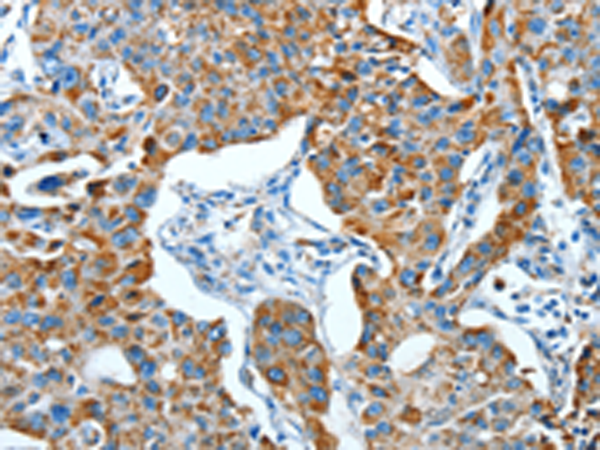

分类: 科研抗体货号: P07817别名: CDG1G; ECM39; hALG12; PP14673应用: IHC反应种属: Human, Mouse